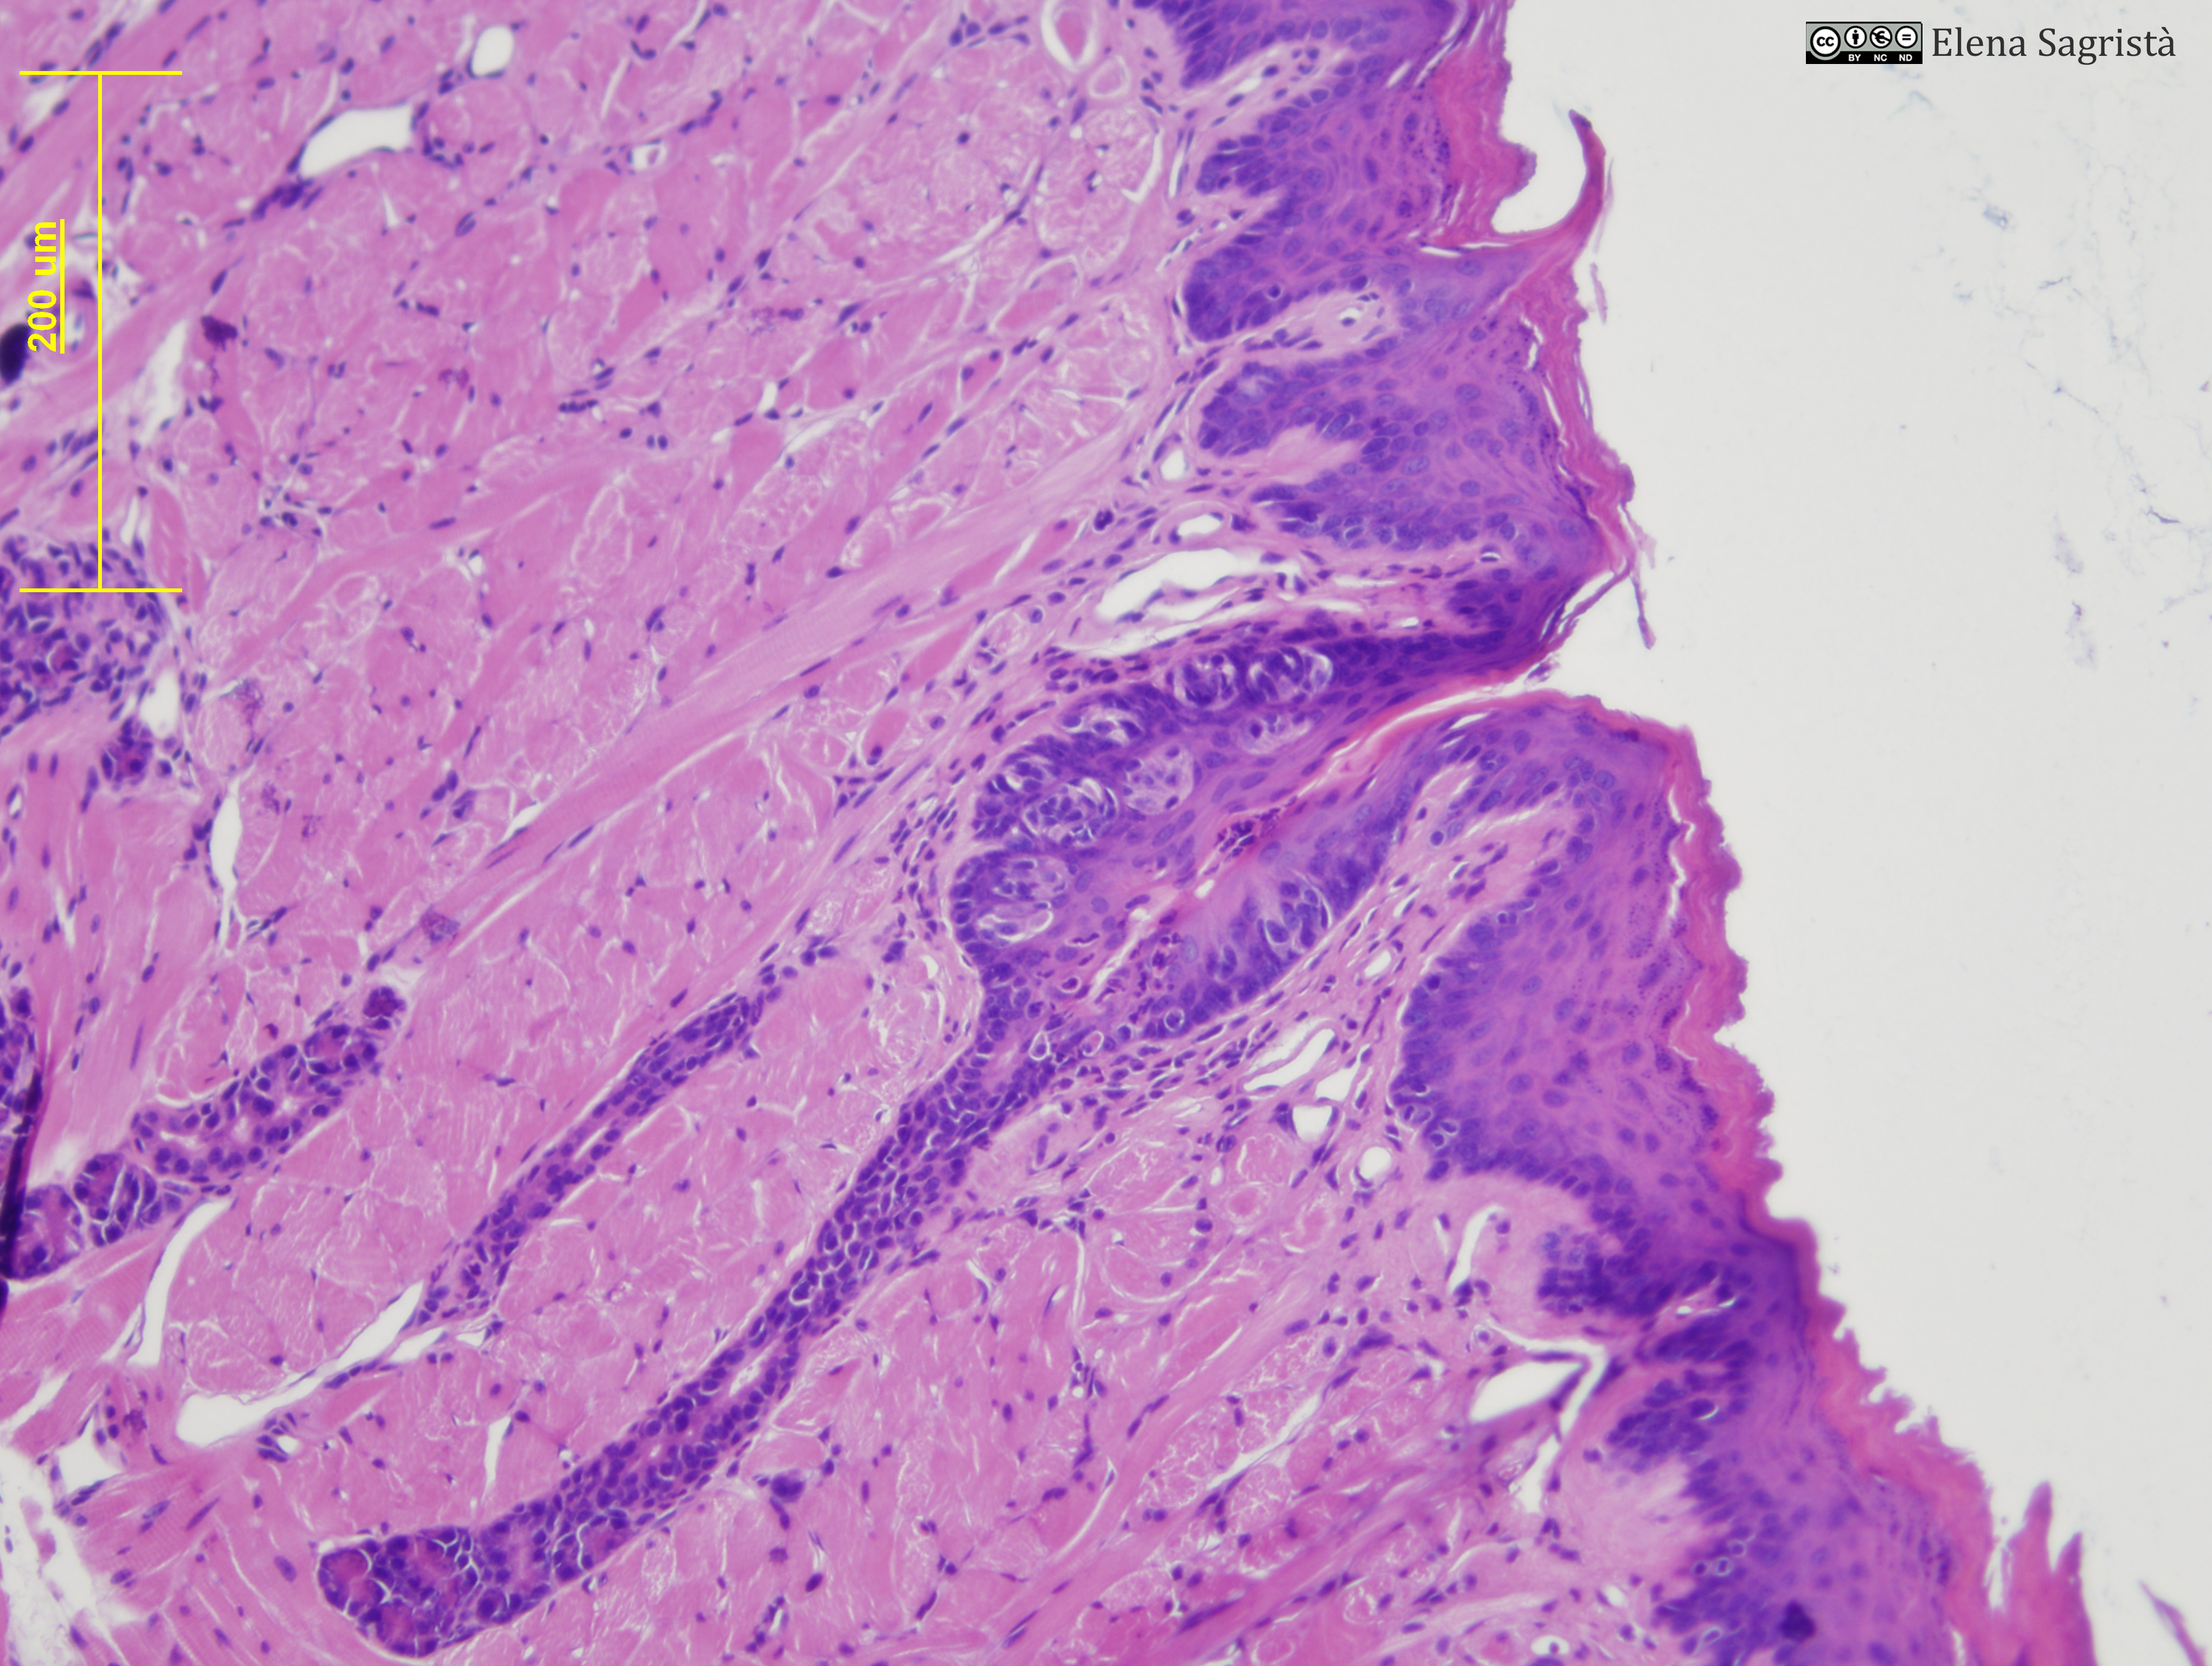

Histologia imatges: 14 Llengua

Imatges de preparacions histològiques de Llengua. Microscopia òptica.